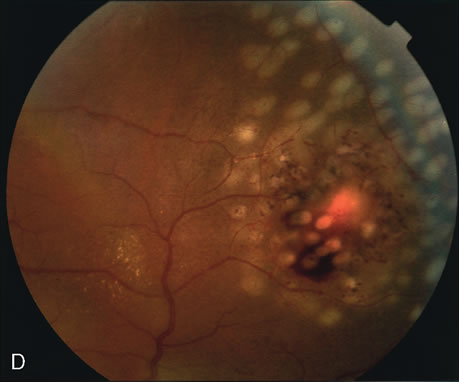

FA is also useful in characterizing two other subgroups of CNV: retinal angiomatous proliferation (RAP)8–16 and polypoidal choroidal vasculopathy (PCV).17–50 RAP begins in the deep retinal complex, forming intraretinal neovascularization (IRN), which may subsequently progress to extend beneath the neurosensory retina, forming subretinal neovascularization (SRN), and a vascularized PED.8 In the later phases of the process there may be a retinal-choroidal anastomosis (RCA). Clinical features of RAP include intraretinal hemorrhages, cystoid macular edema, and associated vascularized PED. FA is useful in revealing the presence of the angiomatous intraretinal vascular complex and the extension of the associated PED (Figs. 12 and 13). However, other diagnostic techniques such as indocyanine green (ICG) angiography, and optical coherence tomography (OCT) may be able to better demonstrate the presence of the RAP lesion.

PCV is characterized by the presence of dilated, choroidal vascular channels ending in orange bulging polyp-like dilations in the peripapillary and macular area. Associated features are recurrent subretinal hemorrhage and vitreous hemorrhage, relatively minimal fibrous scarring, absence of retinal vascular disease, pathologic myopia, and signs of intraocular inflammation. FA demonstrates the presence of the dilated vascular channel (Fig. 14 and 15). However, the presence of blood and exudation may block the details of the choroidal circulation on the angiogram. In these cases, ICG angiography can better demonstrate the presence of a distinct network of vessels within the choroid because the larger choroidal vessels are filled with dye.